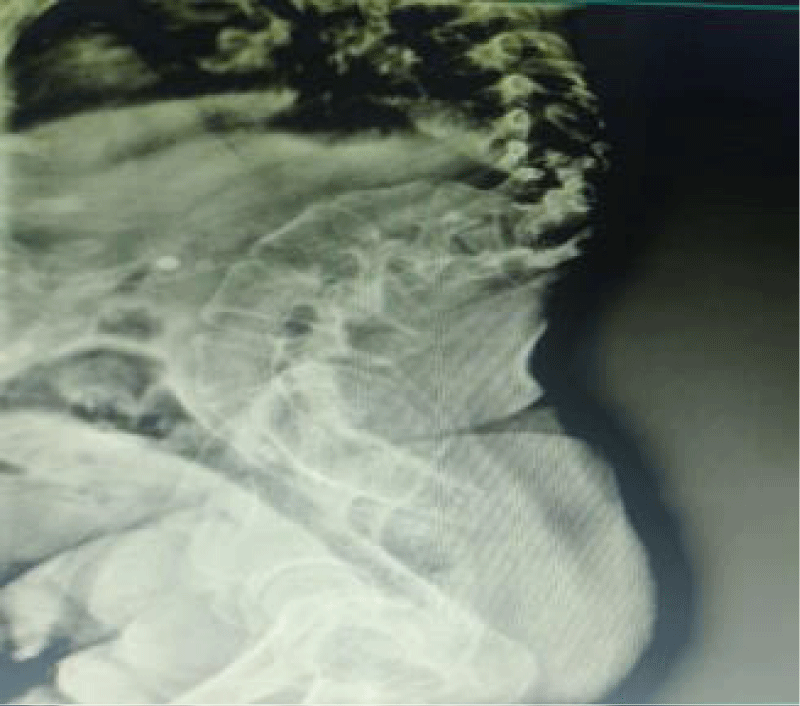

A 30-year - old patient with G3P1L1A at 36 weeks of gestation with kyphoscoliosis, and VSD was identified for emergency LSCS due to preterm labour. She underwent anoplasty at 6 months of age. She had a history of recurrent lower respiratory tract infections. Physical examination revealed short stature (height-120 cm, weight -50 kg), severe thoracolumbar kyphoscoliosis. Airway exam revealed a Mallampati class II airway, 7 cm thyromental distance and intact cervical range of motion. Systemic examination revealed bilateral crackles and a grade III/VI holosystolic murmur along the left sternal border. The electrocardiogram revealed a normal sinus rhythm. A 2D echocardiography revealed an ejection fraction of 65%, a 6 mm apicomuscular VSD with an L->R shunt. X ray thoracolumbar spine showed thoracolumbar curvature is larger and exhibits more rotation with severe thoracolumbar levoscoliosis (Figure 1). Based on the vertebral, anal, and cardiac anomalies, a diagnosis of VACTREL association in parturient was established. After pre-anaesthetic workup and informed consent, she was scheduled for emergency LSCS due to foetal distress. An 18G IV cannula was secured. In the sitting position, spinal anaesthesia was administered via 1.2 cc of hyperbaric bupivacaine and 25 mcg of fentanyl at the L2-L3 space via a paramedian approach with a 25G Quincke’s spinal needle, which was challenging due to anatomical anomalies. Adequate anaesthesia was achieved up to the T6 dermatome. A healthy baby weighing 2.6 kg was delivered with Apgar scores of 8, 9, and 10 at 1, 5, and 10 minutes respectively. For postoperative analgesia, a bilateral transversus abdominis plane block (TAP) was performed under ultrasound guidance.

Figure 1: Lateral standing Lateral X-ray of the spine showing severe thoracolumbar kyphoscoliosis.